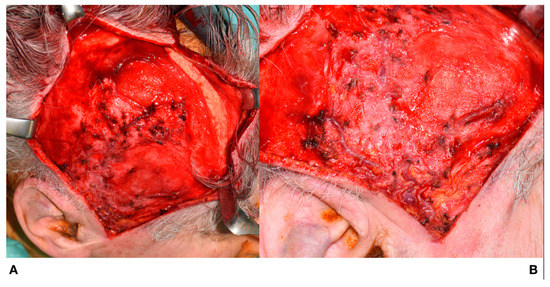

Flap harvesting continued in a cranial–caudal direction; the deep temporal fascia remained attached to the temporal muscle, as shown in Figure 4.

Figure 4.

Flap harvesting. The deep temporal fascia remains attached to the temporal muscle.

The flap was then tunnelled into and rotated within the oral cavity (below the zygomatic arch) to reconstruct the surgical defect, as shown in Figure 6.

Figure 6.

Tunnelling and rotation of the flap. (A): Flap rotation in the oral cavity. (B): Insertion of the flap.

One of the eight flaps included parietal skin, as shown in Figure 7.

Figure 7.

Comprehensive harvesting of a composite skin flap. (A): Augmented reality (AR)-assisted flap design prior to skin incision. (B): Raising of the flap.